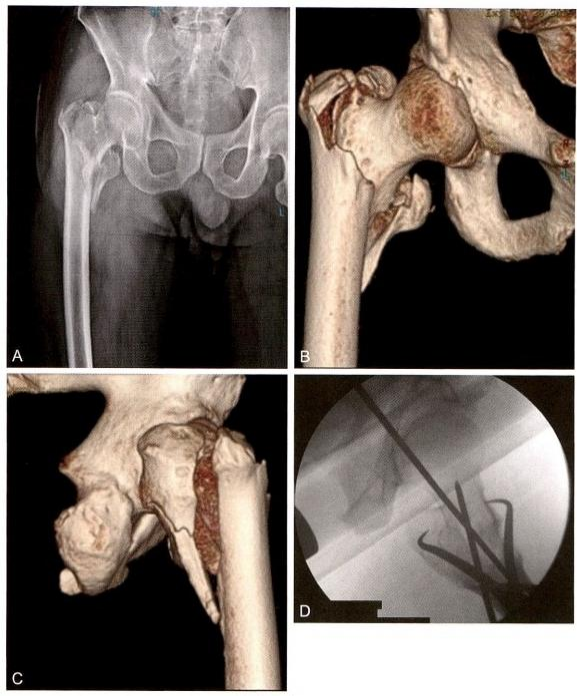

图9-22 全转子区骨折。A.术前X线片,显示为31 A3型骨折;B 、C.术前三维CT示 骨折为全转子区骨折,分别有头颈骨块、股骨干骨块、小转子骨块、外侧壁骨块,前 壁骨块大转子分裂为前后2块;D~F. 采用mimics软件模拟骨折复位,显示骨折粉碎 程度

图9-22 ( 续 )G 、H. 闭合复位获得良好对线之后,微创导入钢丝,准备捆扎收拢小转 子骨块;I. 头髓钉手术之后,收紧小转子钢丝,但捆扎在髓内钉主杆上。为了避免干 扰骨折愈合,将其拆除;J 、K 、L. 术毕透视正位、侧位和前内侧斜位,示内芯螺钉拧 紧,远侧交锁螺钉打入在动力位;M 、N. 术后第5天拍片,示环周骨皮质缺损很多;O 、P. 术后三维 CT 显示仅前内下角约1/6的环周皮质相互抵住

图9-22 ( 续 )Q 、R.三维CT透明处理显示头髓钉内固定位置良好,髓内钉充满髓腔, 消除了髓内钉的摆动(雨刷效应);S 、T. 术后7个月,透视示股骨颈无短缩,内侧股 骨距愈合良好,外侧壁也出现骨桥连接。注意:与术后即刻相比,交锁螺钉上移